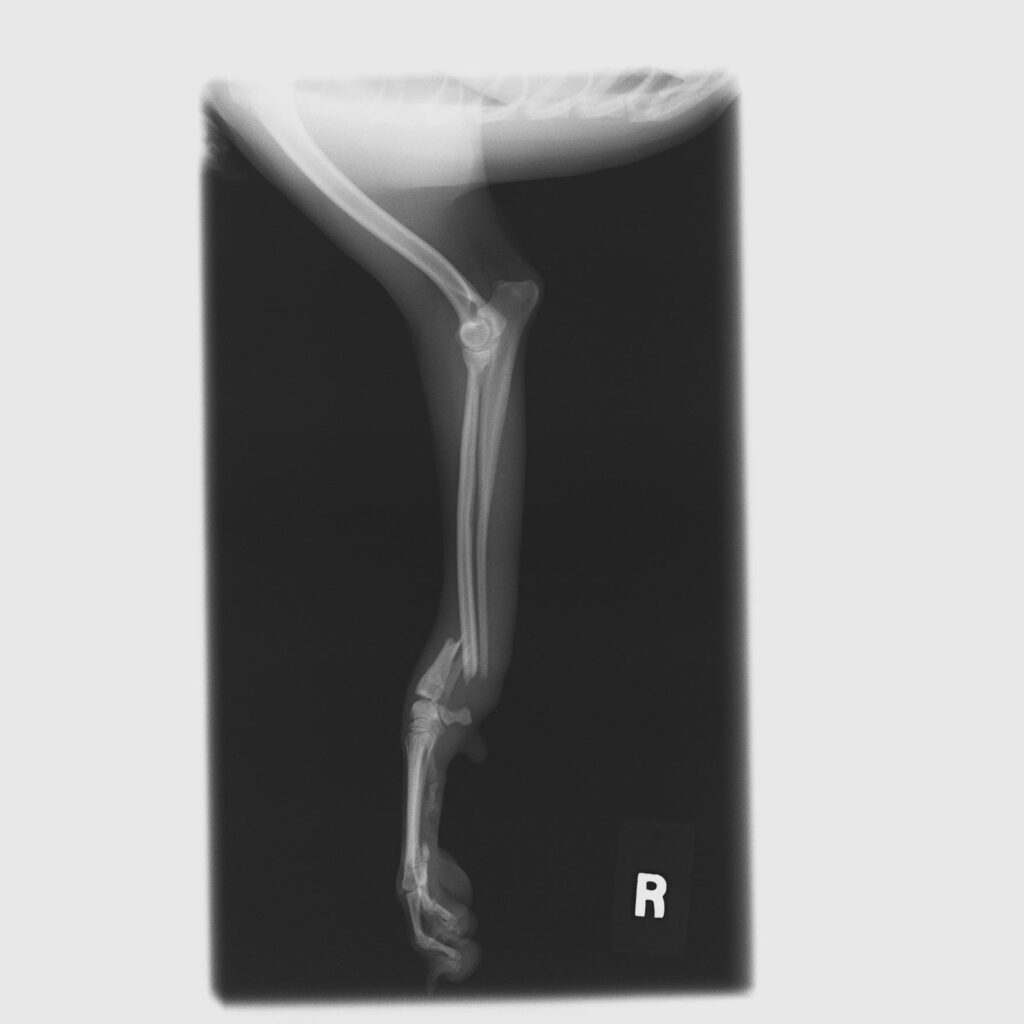

犬_整形外科_20260310 162831_診察前

処置前

診察および検査の結果、以下の異常が確認されました。

• 橈尺骨折

橈骨および尺骨に骨折が認められ、外科的な整復が必要な状態でした。